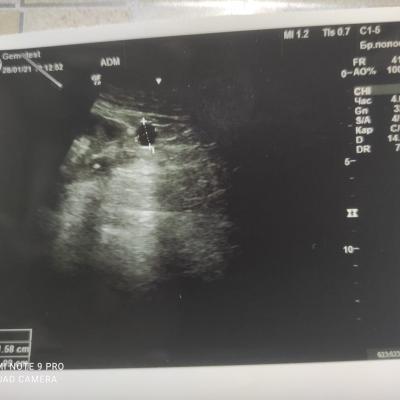

Здравствуйте! При наличии коралловидного камня правой почки(заключение УЗИ), можно предположить причиной боли нарушение уродинамики верхних мочевых путей), что, однако, не подтверждается результатами УЗИ почек( ЧЛС не расширена). Другая, наиболее вероятная возможная причина "боли в боку" - может быть патология опорнодвигательного аппарата. Необходимо проконсультироваться с неврологом и урологом очно, и согласовать возможность применения противовоспалительных, обезболивающих и спазмолитических препаратов - как первый шаг. В дальнейшем необходимо планировать возможное дальнейшее обследование и лечение. Удачи!